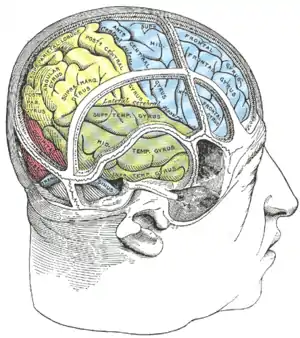

Superior temporal gyrus of the human brain. | |

Lateral view of a human brain, main gyri labeled. Drawing of a cast to illustrate the relations of the brain to the skull. (Superior temporal gyrus labeled at center, in green section.)